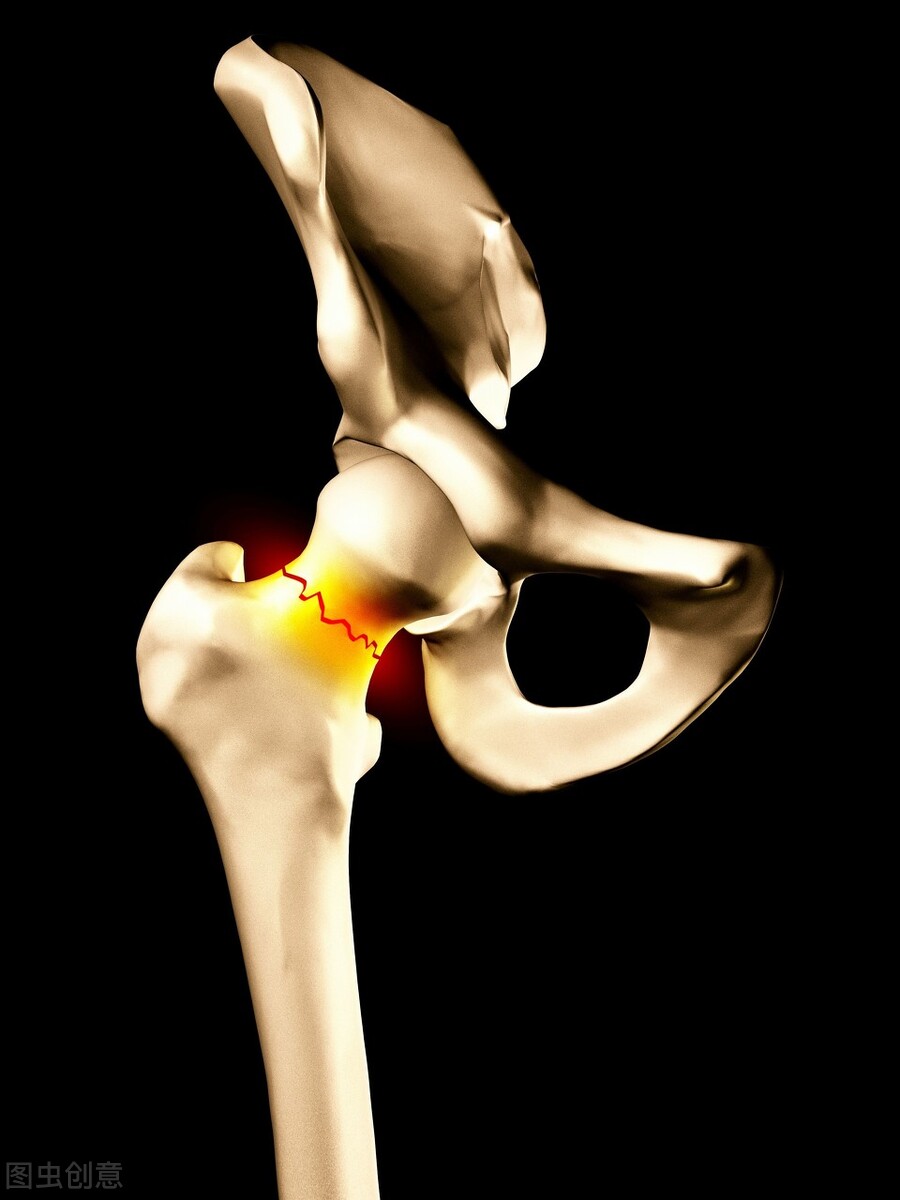

骨折发生率最高的是哪儿?是四肢,当然颅骨、肋骨、胸骨、骨盆,还包括脊柱等等其他部位也可以发生骨折,但是四肢骨骨折率最高。 以前大家没有急救意识,遇到这样的情况,经常好心干坏事,比如说有人被车撞了,大腿骨折了,赶紧截个车,一个人抱上面,一个人抬腿,给抬到车上,他的大腿本来就骨折了,可能没移位,这样一抬就移位了,造成畸形了。如果已经移位了,这样一抬就会加重异位,周围的血管、神经的损伤就会加重,或者本来没有损伤,这样一抬就造成损伤了,这都是教训。